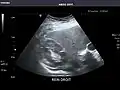

Right kidney -